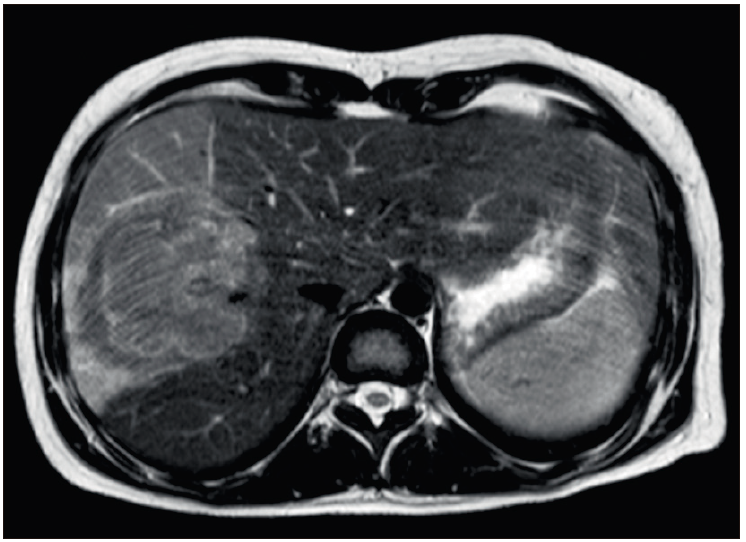

Se realiza una tomografía de tórax, abdomen y pelvis con contraste oral y endovenoso (Figura 1), en la que se observa una formación voluminosa de 9 cm, de contornos lobulados, heterogénea y con área central hiperdensa. Se prosigue a realizar una resonancia de abdomen trifásica, en la cual se observa una lesión sólida de contornos irregulares y señal heterogénea de 55 x 56 x 50 mm, hipervascular, con realce capsular periférico tardío, múltiples imágenes nodulares satélites y trombosis de la vena porta derecha (Figuras 2a, 2b y 2c).

Figura 2a. Imagen en plano axial de resonancia magnética ponderada

en secuencia T2, que demuestra una masa en el lóbulo hepático derecho con una señal levemente

hipointensa y heterogénea con un halo de mayor señal periférica. La baja señal puede reflejar un

componente fibroso o bien hipercelularidad. El parénquima circundante presenta una leve hiperintensidad

difusa, que probablemente refleja edema, inflamación o hiperemia